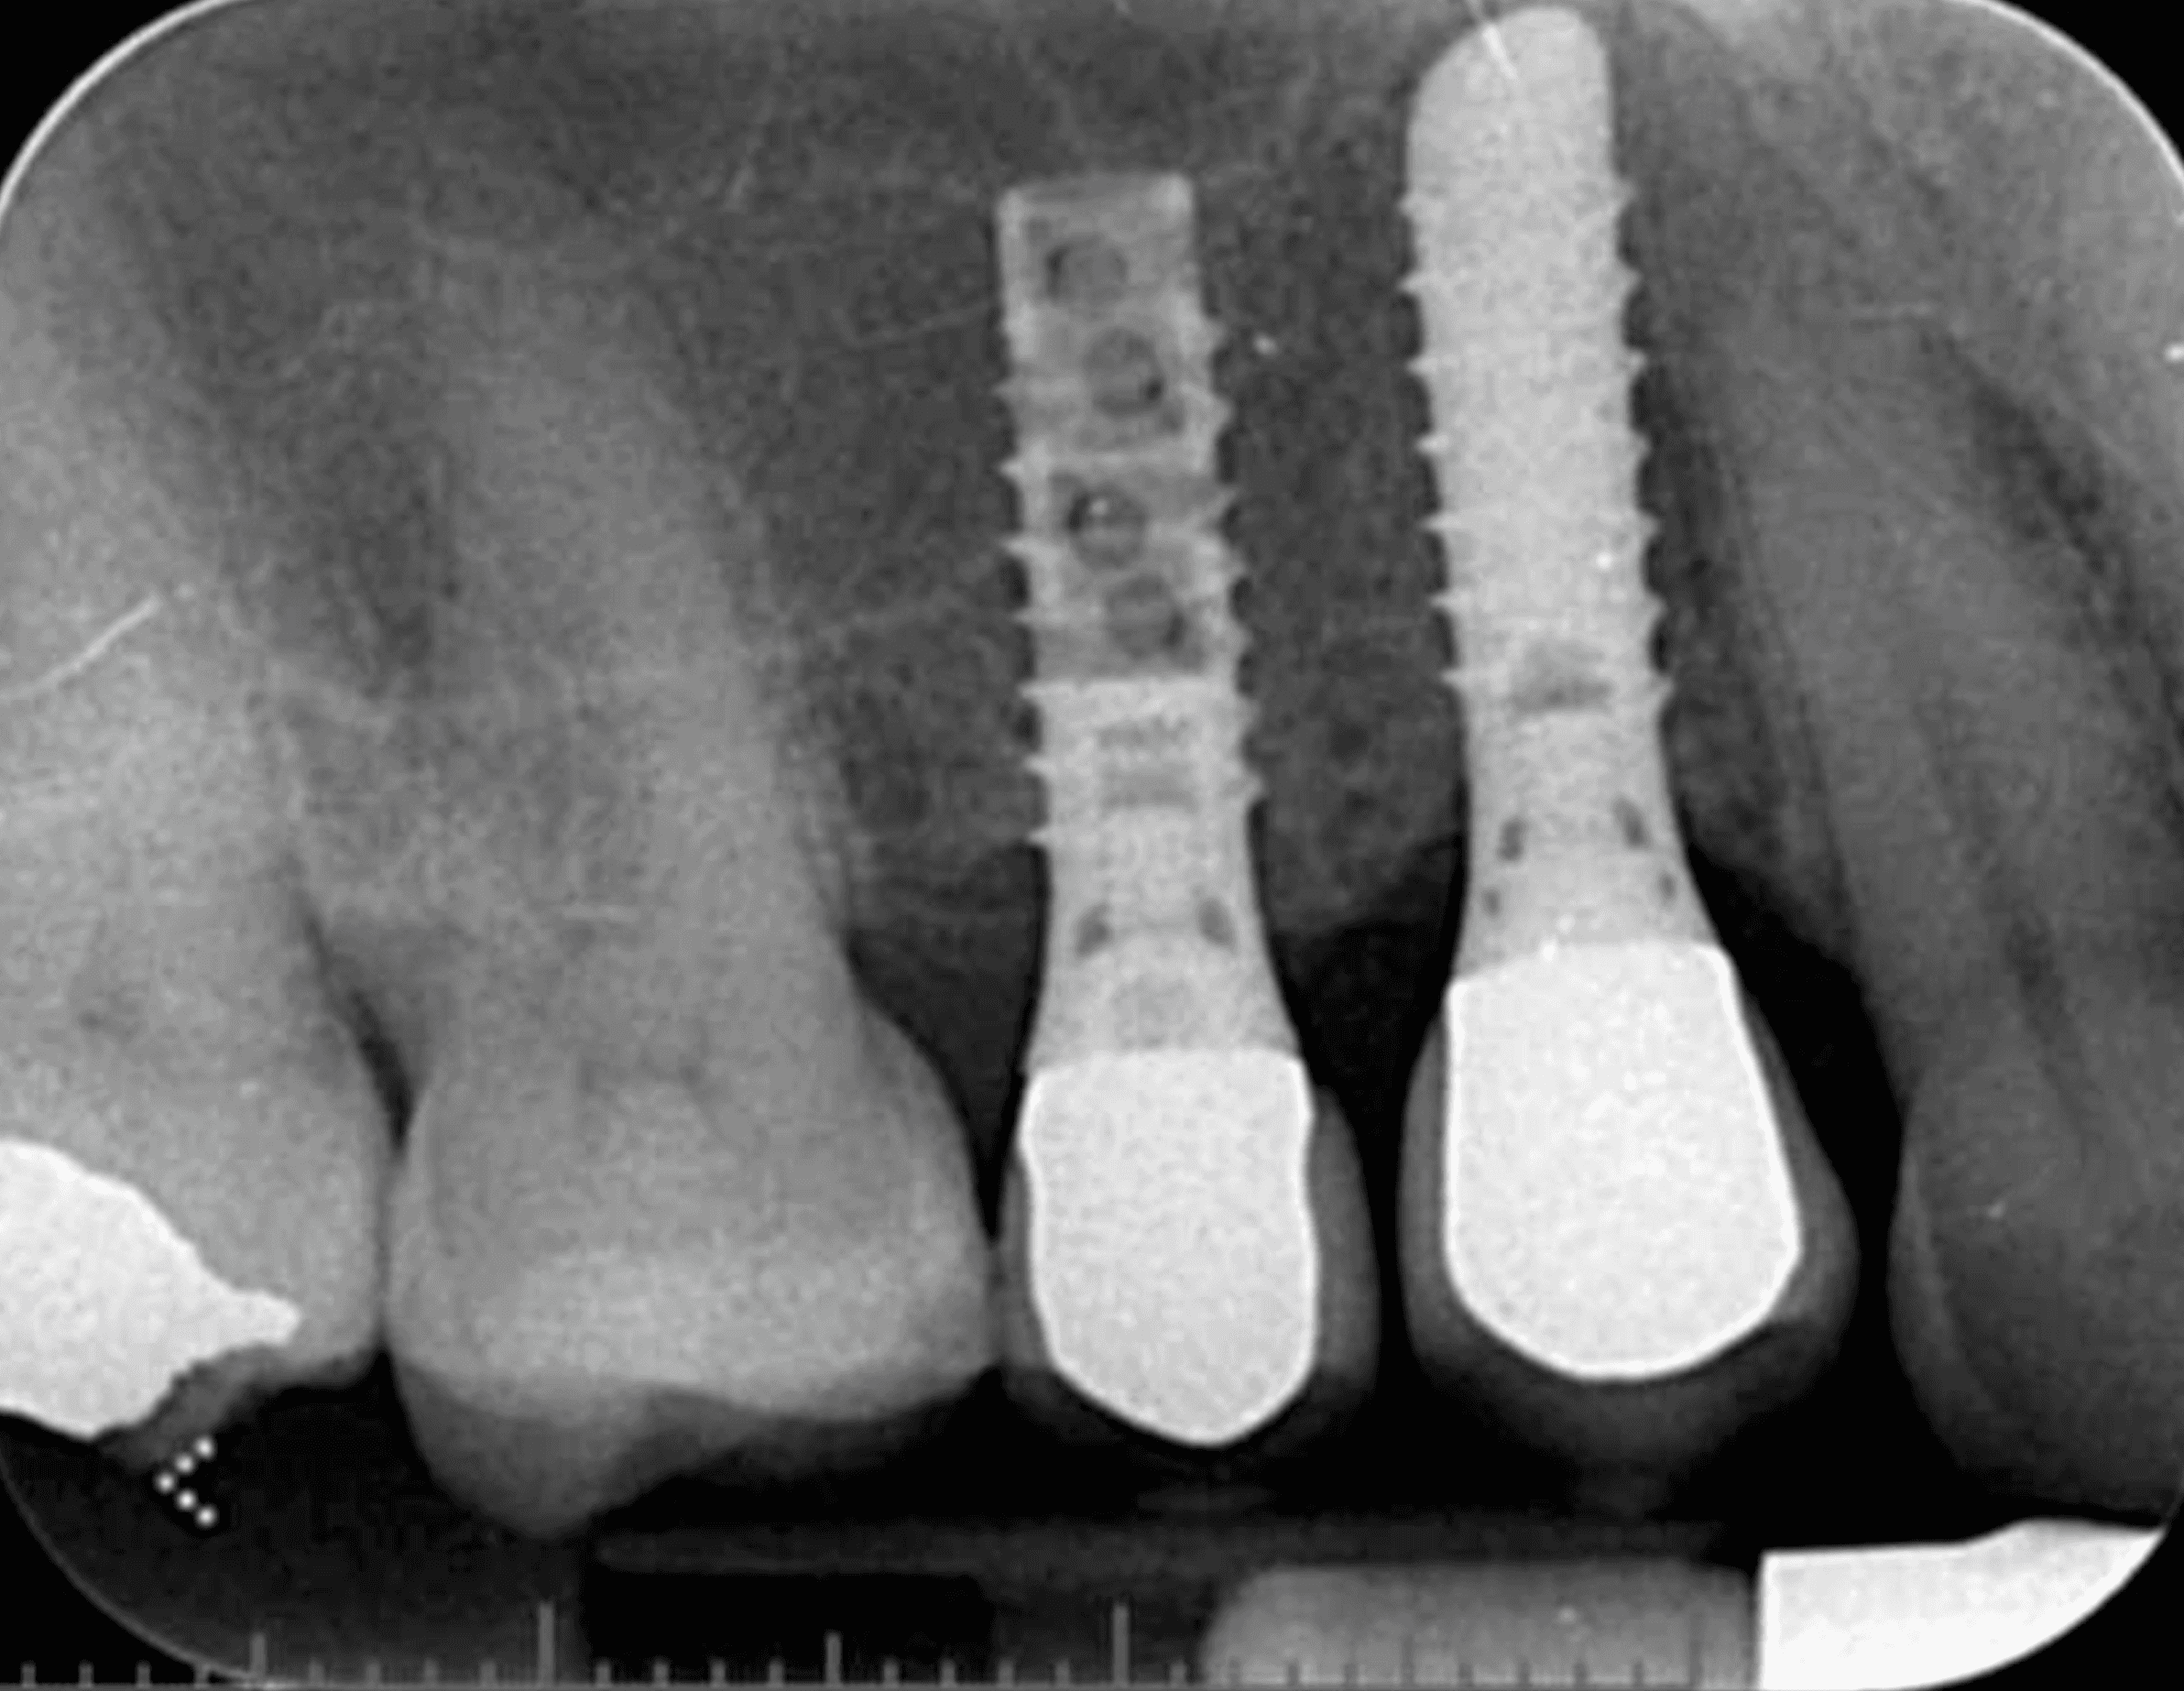

즉시 보철 임플란트는 임플란트 수술 후 잇몸이 아물기를 기다렸다가 보철물을 연결하는 기존 방식과 달리,

임플란트 식립과 동시에 임시 보철물(임시 치아)을 연결하여 바로 외모 개선 및 제한적인 저작 기능을 회복할 수 있도록 하는 치료 방법입니다.

수술 횟수↓: 발치·식립·임시 치아를 원스톱으로